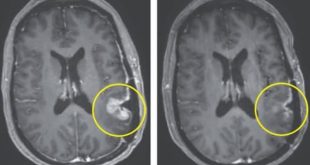

বর্তমান সময়ে ভালোবাসার সম্পর্কগুলো একরকম ঠুনকোই হয়ে গেছে বলা যায়। চারদিকে চোখ রাখলেই বিবাহবিচ্ছেদ-সংসার ভাঙনের মহাসমারোহ নজরে আসে। তবে এসবের মাঝেও অনেক দম্পতির মাঝে ভালোবাসার অনুপম নিদর্শন চোখে পড়ে। যেমনটা এবার দেখা গেল এক ভারতীয় দম্পতির ক্ষেত্রে। কিডনির সমস্যার কারণে …